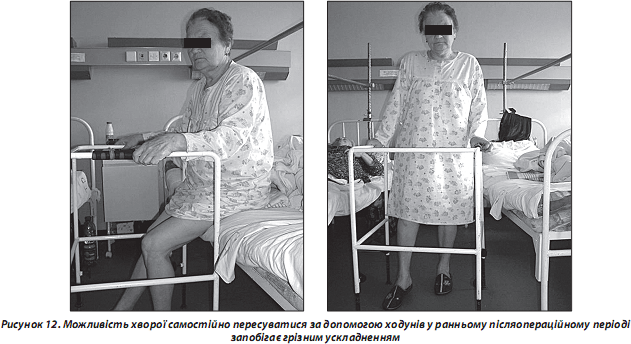

Окрім перелічених проблем, слід згадати і про особливості функціональної реабілітації хворих літнього віку з переломами проксимальної ділянки стегнової кістки (рис. 12). Проблема актуальна і складна, оскільки кількість людей з такими травмами нижніх кінцівок постійно зростає. Реабілітація є особливо важким завданням ще і тому, що переломи кісток нижніх кінцівок у 60–72 % хворих супроводжуються стійкими розладами рухової функції і різко обмежують можливості самостійного пересування на тривалий час, що призводить до інвалідизації.